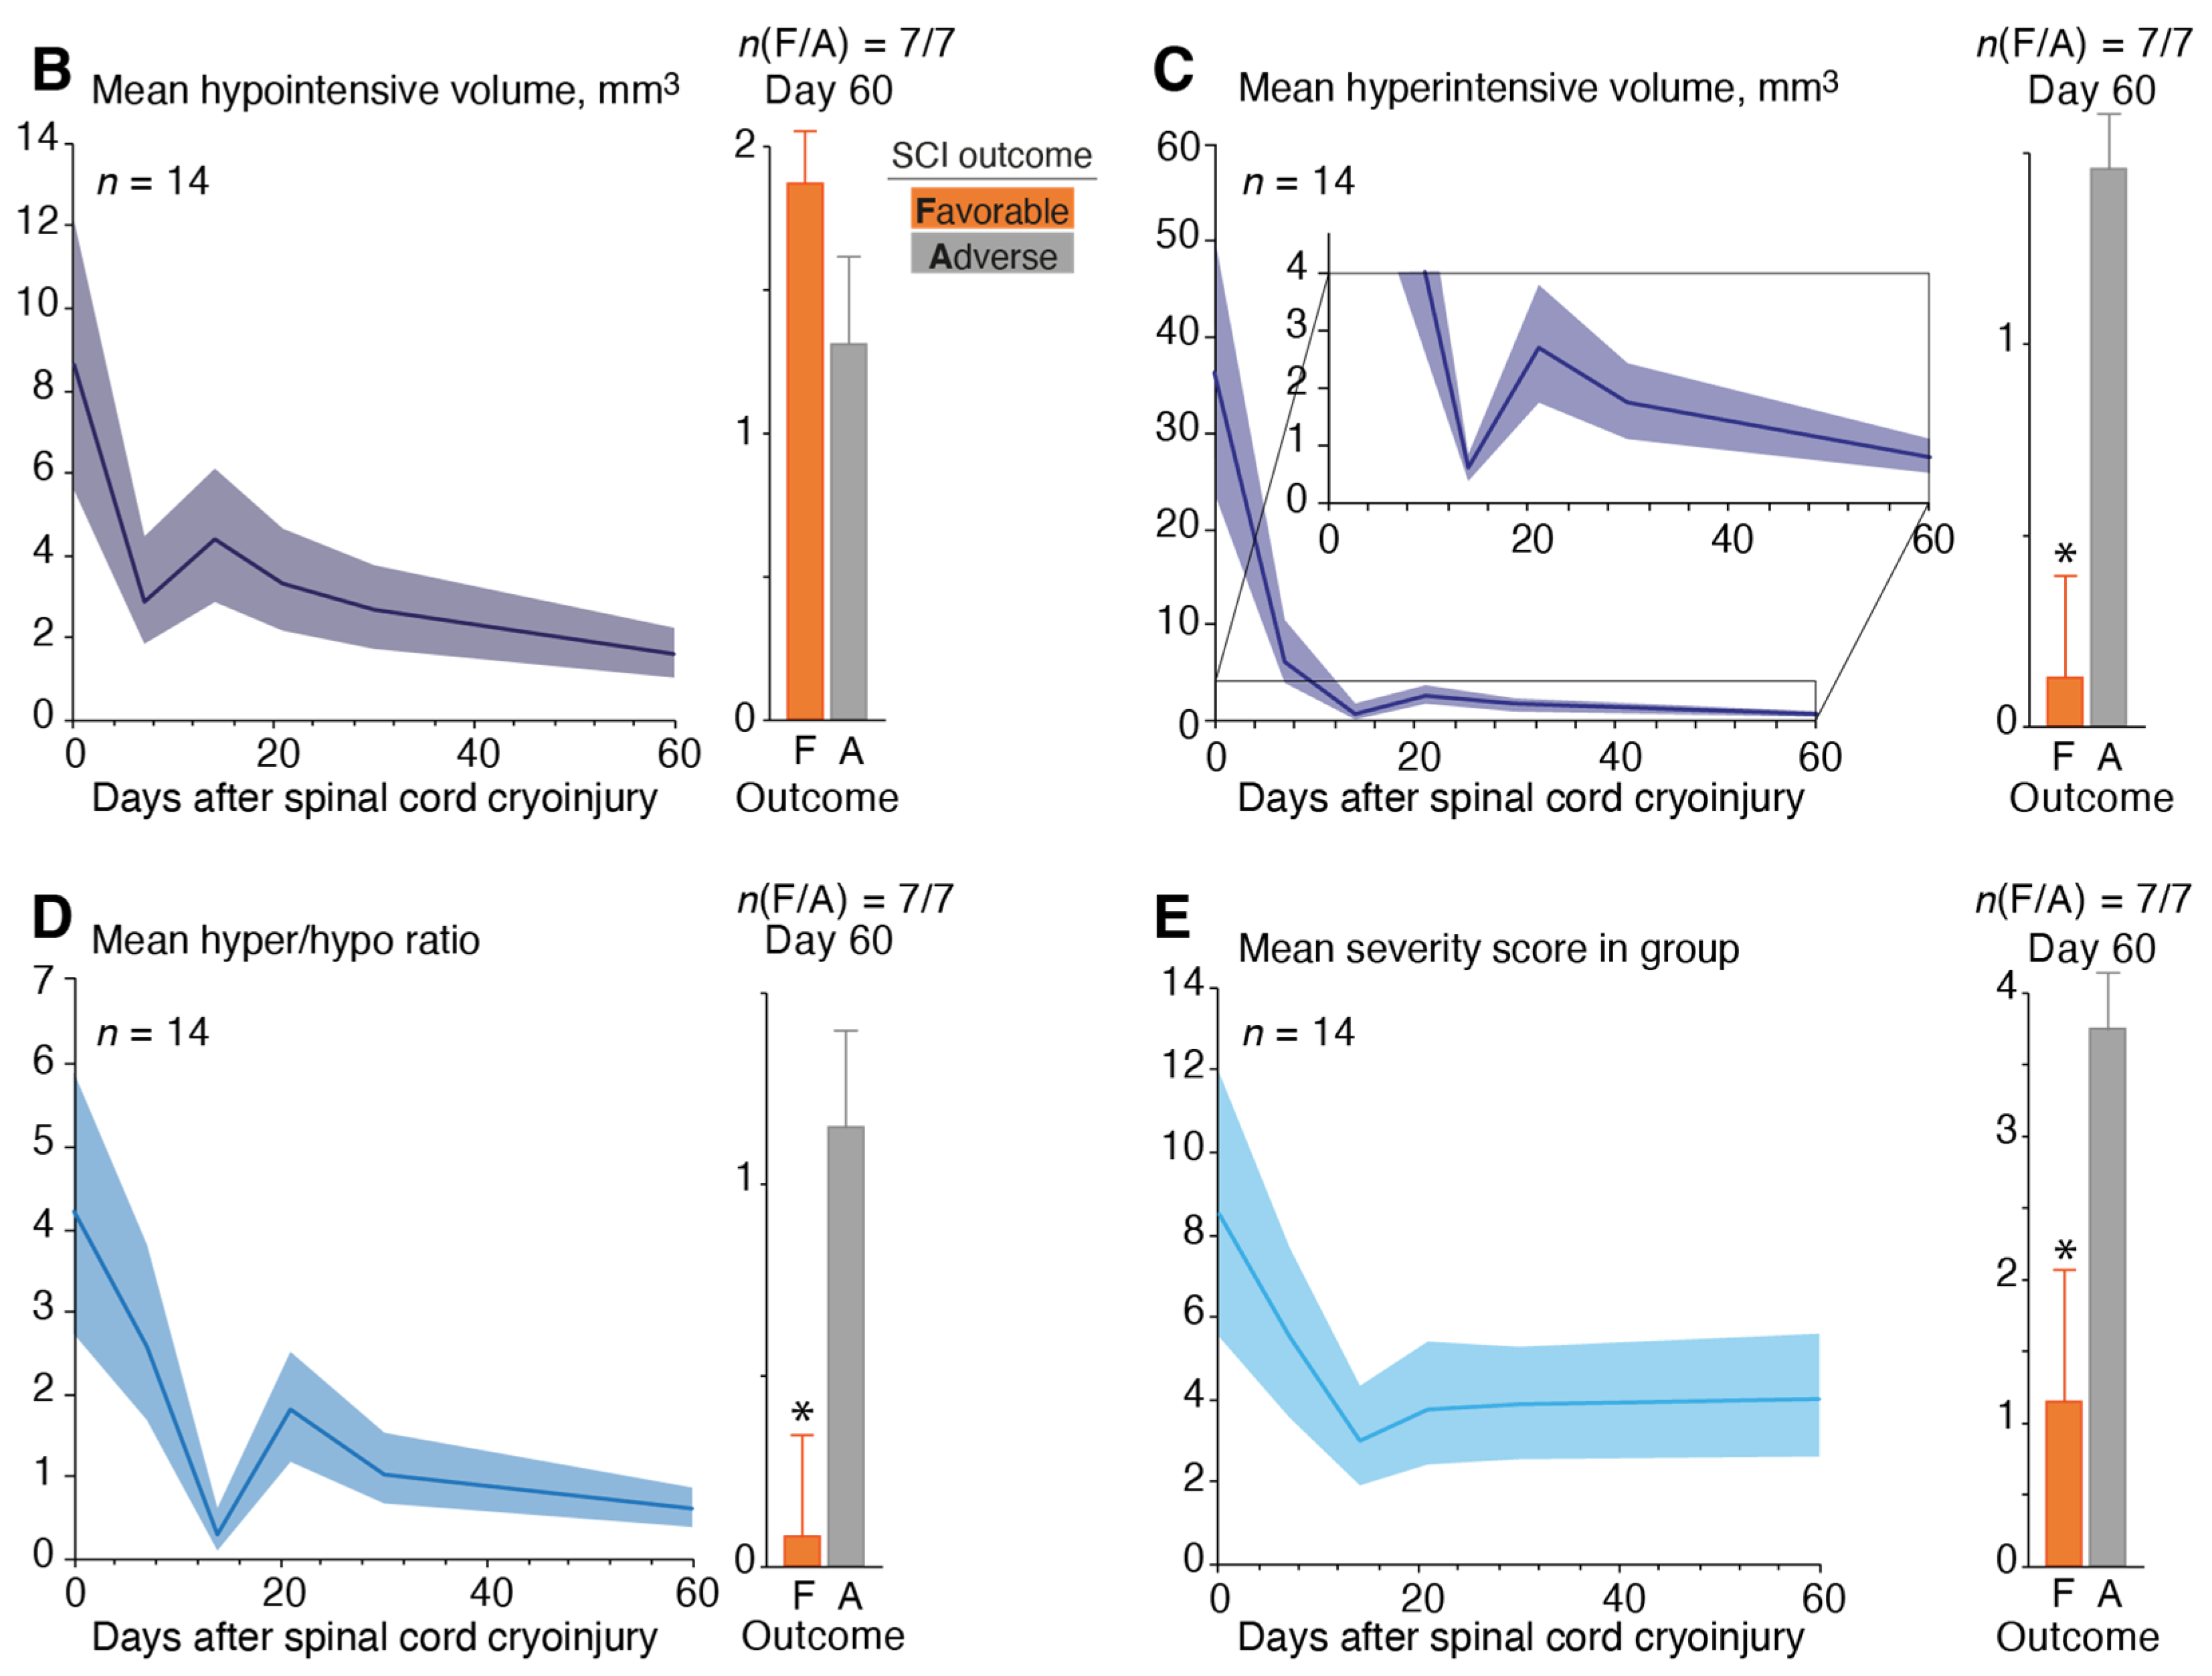

3.3. Magnetic Resonance Imaging of the Spinal Cord Cryoinjury